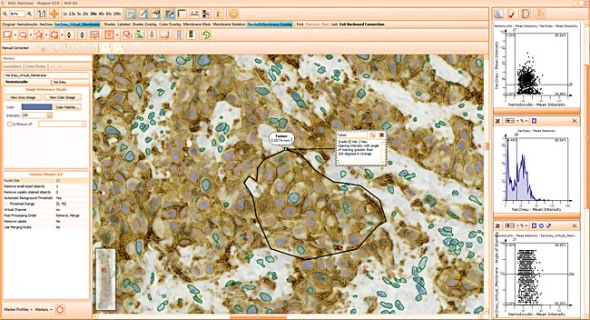

Context-based analysis can be done by manually drawing regions of interest. TMA can be analysed and also detected on imported files.

Combined with segmentation images it is also a simple and intuitive tool to visually validate results. TG calls this "Backward Gating".

The following examples show Backward Gating versatility on segmented nuclei positive for Ki-67. Backward gating can be done for any measured parameter on histograms and scattergrams.

Simple context based analysis can easily be done in HistoQuest by using manual region tools. Drawing the regions takes a negligible amount of time and provides data for epithelial areas and stroma separatelyin this example.

The skeleton algorithm permits the detection of membrane stainings (see image above).